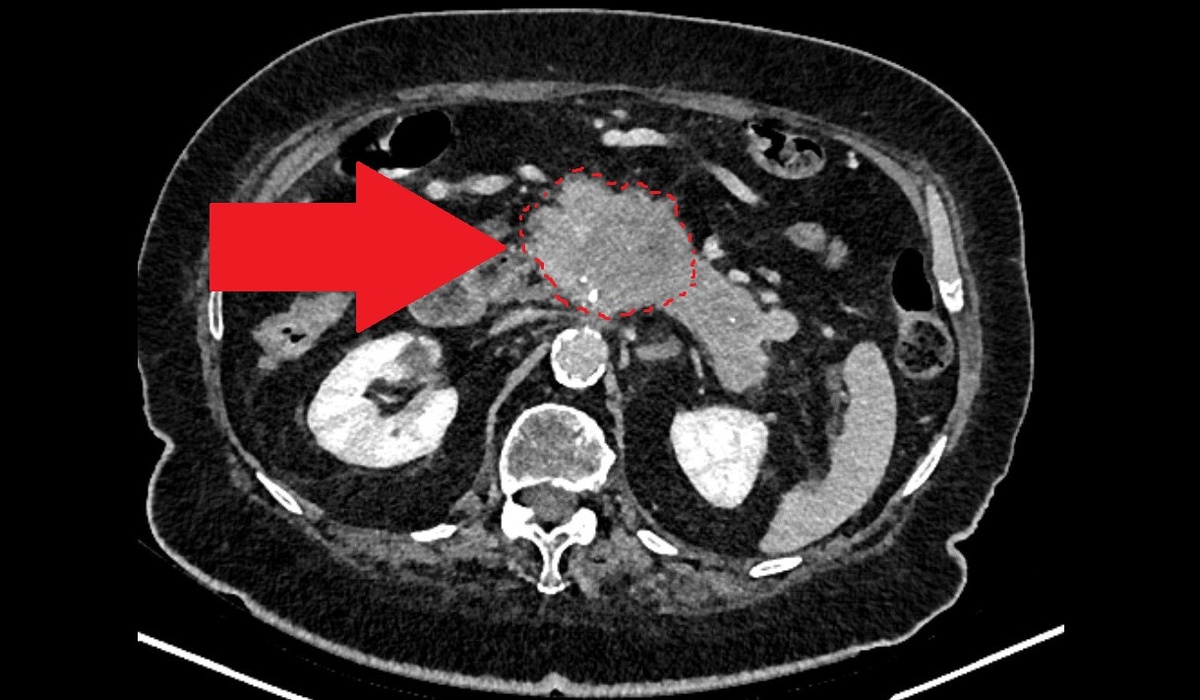

При компьютерной томографии была выявлена крупная опухоль в поджелудочной железе: размеры опухоли в наибольшем измерении превышали 10 см. Как ни странно, ни желтухи, ни выраженного болевого синдрома у пациентки при этом не было.

Вовлечение магистральных сосудов указывает на неоперабельность опухоли, то есть технически такую опухоль удалить невозможно.

Пунктиром указаны примерные границы опухоли поджелудочной железы.